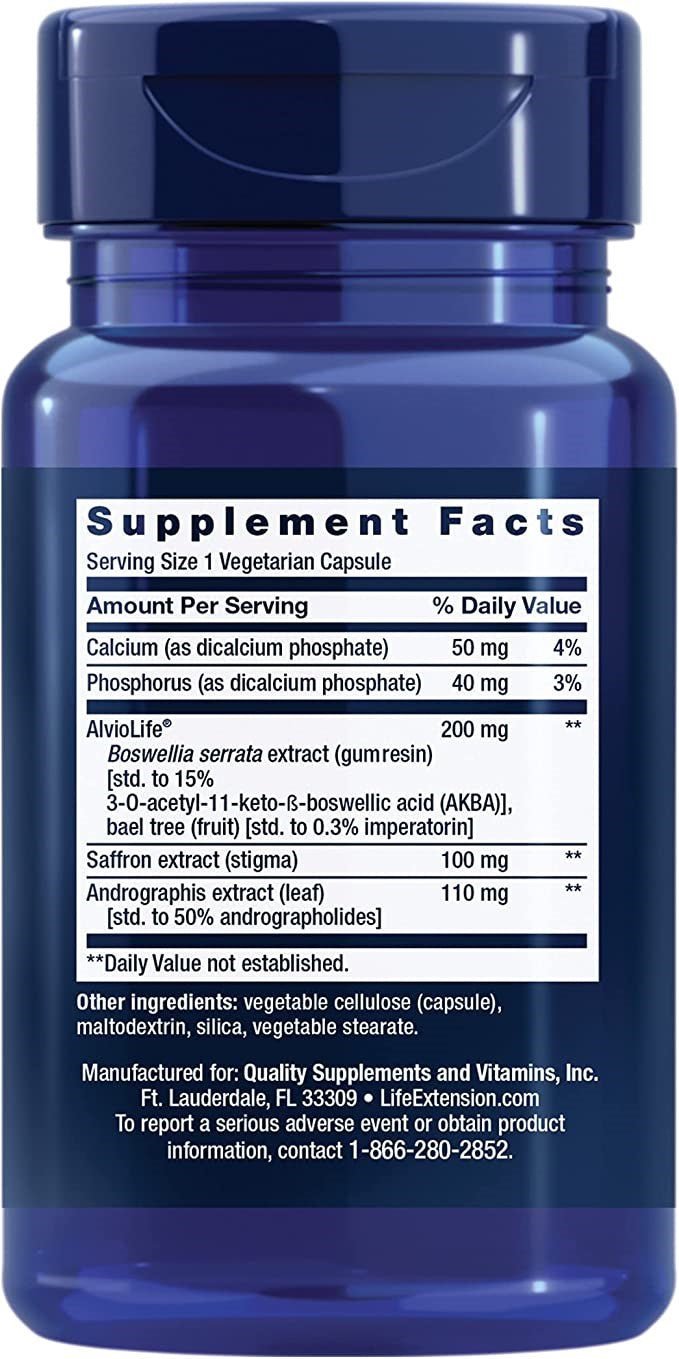

Contenu par capsule

Calcium (sous forme de phosphate dicalcique) – 50 mg

Phosphore (sous forme de phosphate dicalcique) – 40 mg

AlvioLife® (résine de Boswellia serrata + extrait de fruit d'Aegle marmelos) – 200 mg

Extrait de safran (stigmatisation) – 100 mg

Extrait d'Andrographis (feuille, standardisé à 50% d'andrographolides) – 110 mg

Autres ingrédients : Gélule végétale (hydroxypropylméthylcellulose), maltodextrine (charge), dioxyde de silicium (antiagglomérant), stéarate végétal (stabilisant).